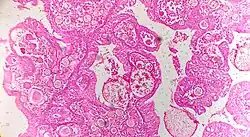

Renal cell carcinoma | Micrograph of clear cell renal cell carcinoma showing cells with clear cytoplasm, typically arranged in nests and nuclear atypia. | Category: Histopathology of renal cell carcinoma | Renal cell carcinoma |

| Cresenteric glomerulonephritis | Photomicrograph of the renal biopsy showing prominent fibrocellular crescent formation and moderate mesangial proliferation in a glomerulus. | Category: Histopathology of glomerulonephritis | glomerulonephritis | |